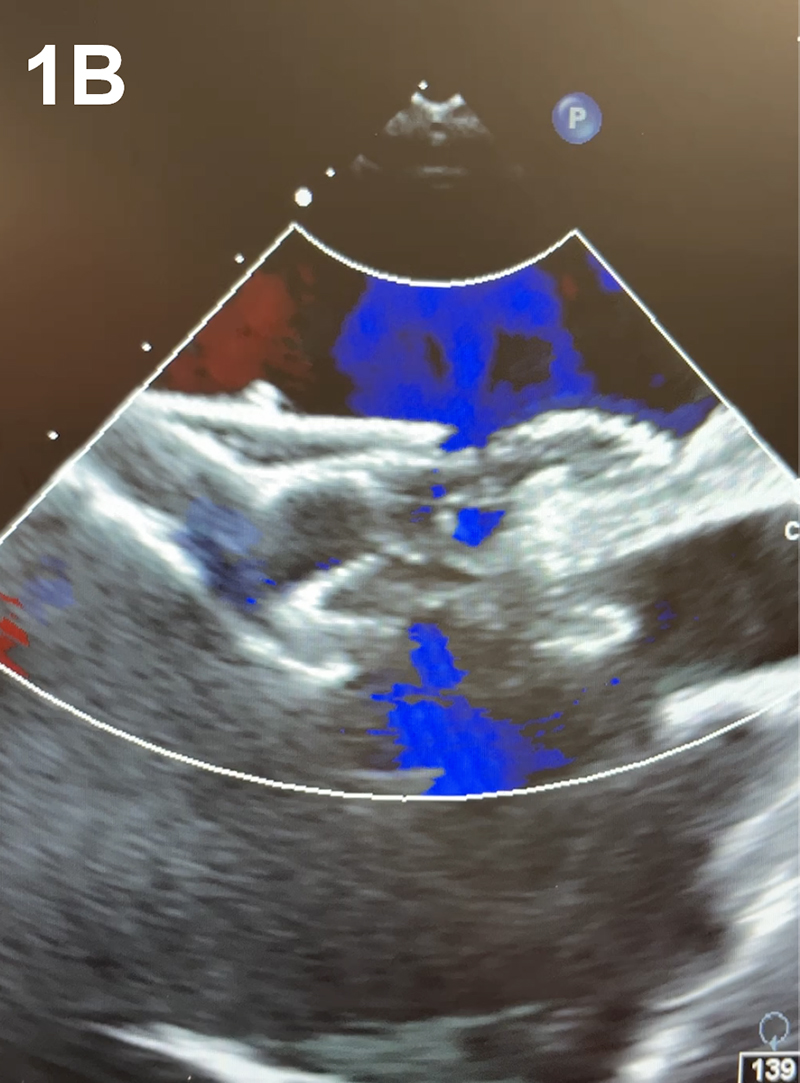

A 41-year-old man with no significant past medical history presented with a cryptogenic cerebrovascular accident (CVA). Brain magnetic resonance imaging (MRI) revealed small, multiple infarcts in the left frontoparietal white matter. Transthoracic echocardiography (TTE) demonstrated right heart enlargement, a large patent foramen ovale (PFO) with an atrial septal aneurysm (ASA) and high-risk features for paradoxical embolism. Planned percutaneous PFO closure was modified intra-procedurally when transesophageal echocardiography (TEE) revealed two distinct ostium secundum ASDs (Figure 1A–B). Right and left atrial pressures measured 10 mmHg and 18 mmHg, respectively. The 21 mm and 8 mm defects were consistent with a large fenestrated ASD with predominant left-to-right shunting. Dual-device closure was pursued to ensure complete occlusion. A 24 mm Amplatzer septal occluder (ASO) was deployed for the larger defect, and a 30 mm cribriform ASO for the smaller defect (Figure 1C–D). TEE confirmed stable device positioning and complete closure with no residual shunting. The patient tolerated the procedure well with no complications.

Figure 1. (A–D) Two-dimensional transesophageal echocardiography (TEE) with color Doppler demonstrates two distinct atrial septal defects with left-to-right shunting (A). TEE confirms successful closure of both defects following implantation of dual Amplatzer septal occluder devices (C). Fluoroscopic imaging during the procedure shows the positioning of both occluder devices (D).